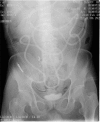

Presentation of case: A 75-year-old man undergoing treatment for alcoholic cirrhosis underwent laparoscopic abdominoperineal resection of the rectum (APR) for lower rectal cancer after preoperative chemoradiotherapy. Lung metastases were diagnosed 2 months postoperatively. Ten days after chemotherapy initiation, the patient was hospitalized on an emergency basis due to hepatic encephalopathy. Ten days thereafter, we observed perineal skin protrusion. Moreover, the skin disintegrated spontaneously, resulting in ascetic fluid outflow. Pain and fever developed, with inflammatory reactions. Contrast-enhanced computed tomography showed strangulated small bowel obstruction due to perineal hernia. We performed an emergency surgery, during which we found small intestine wall incarcerated in the pelvic dead space, with thickening and edema; no necrosis or perforation was observed. We performed internal fixation by introducing an ileus tube into the ileocecum and fixing its balloon at the cecal terminus.